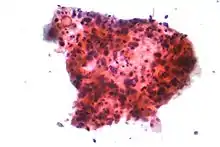

Lung cancers are classified according to histological type.[6] This classification is important for determining both the management and predicting outcomes of the disease. Lung cancers are carcinomas – malignancies that arise from epithelial cells. Lung carcinomas are categorized by the size and appearance of the malignant cells seen by a histopathologist under a microscope. For therapeutic purposes, two broad classes are distinguished: non-small-cell lung carcinoma and small-cell lung carcinoma.[70]

In SCLC, the cells contain dense neurosecretory granules (vesicles containing neuroendocrine hormones), which give this tumor an endocrine or paraneoplastic syndrome association.[75] Most cases arise in the larger airways (primary and secondary bronchi).[17] Sixty to seventy percent have extensive disease (which cannot be targeted within a single radiation therapy field) at presentation.[1]